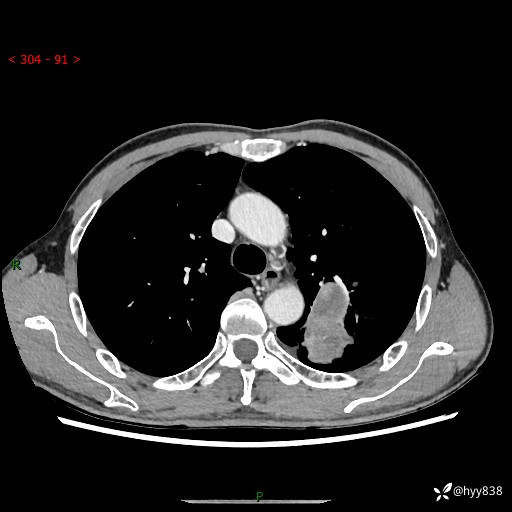

现病史:患者余4月前发现咳嗽咳痰伴痰中带血,无胸闷、胸痛、头晕、恶心、呕吐等不适,2天前因体检发现肺部结节遂于当地市第一人民医院行胸部CT薄层平扫+三维重建示:1.左肺上叶尖后段占位性病变考虑肿瘤性病变伴阻塞性肺炎,右肺上叶后段磨玻璃结节。2.肝内多发囊性灶、左肾结石。现患者为求进一步治疗,于我院门诊就诊,门诊以“肺结节”收入院。 自患病以来,精神、饮食、睡眠尚可,大小便正常,体力体重无明显减轻。

胸部CT增强扫描(外院平扫)